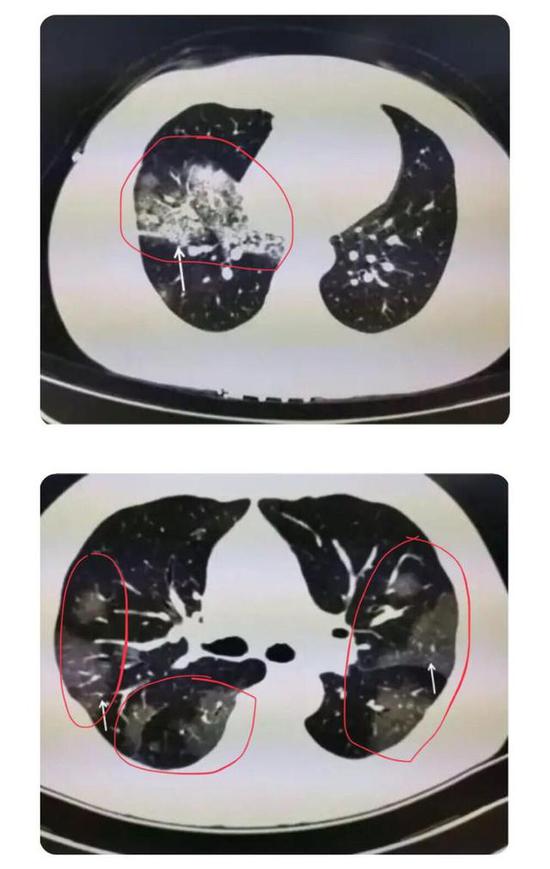

根據感染程度不同,有的僅單側肺出現這種磨玻璃影,還有的雙側都有。磨玻璃影可以累及一個肺葉,也可同時累及多個肺葉。

▲上面的圖:單側肺出現磨玻璃影,累及一個肺葉;下面的圖:雙側肺均出現磨玻璃影,累及多個肺葉(圖片來自網絡)

上海市胸科醫院放射科主任醫師于紅在接受媒體采訪時介紹,新冠肺炎的影像特征與其他病毒性肺炎相似。早期患者肺部多會出現單個或多個小斑片影、局灶性磨玻璃影等。隨著病情進展,病灶增多并融合,范圍擴大,多個肺葉出現小斑片,或者表現為彌漫性磨玻璃影及實變結節影。